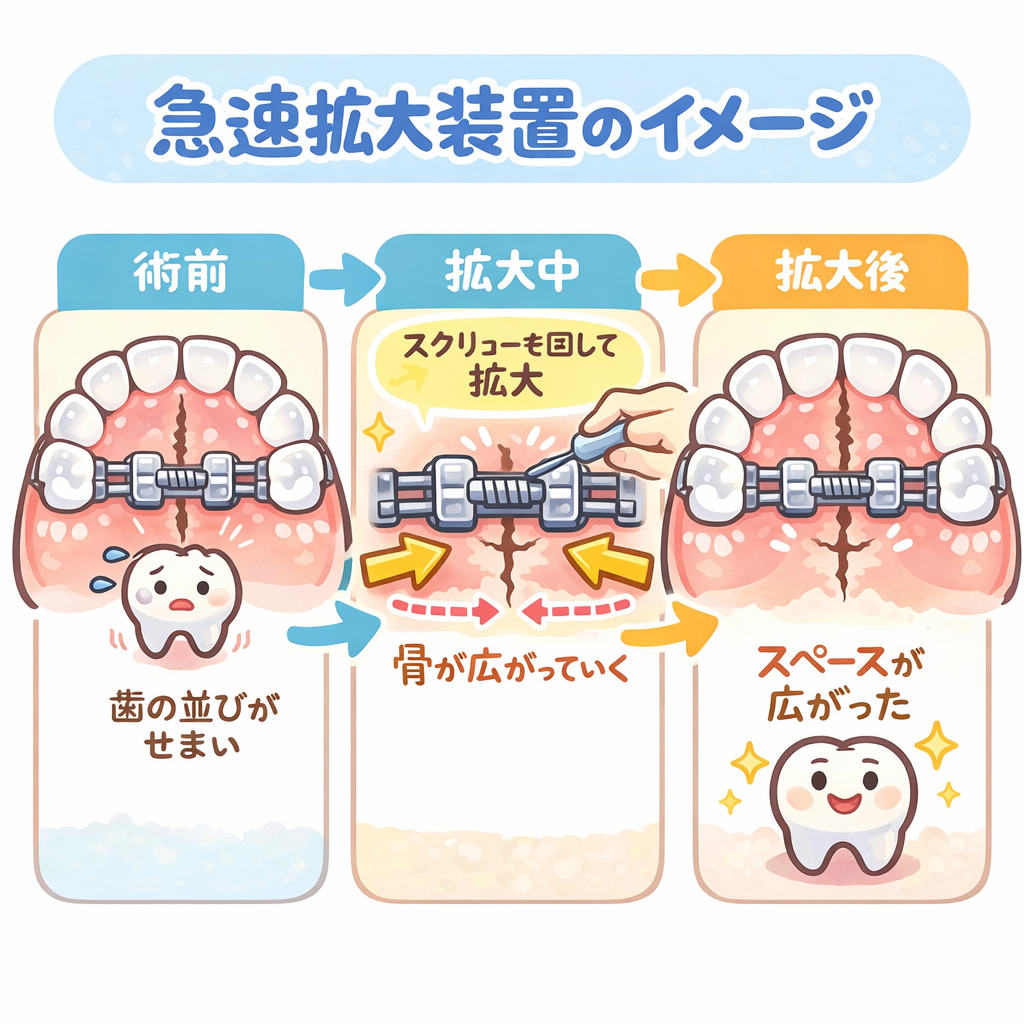

●急速拡大装置

急速拡大装置は、接着剤で歯にくっつける固定式の拡大装置です。

急速拡大装置は強い力が発揮できる拡大装置で、上顎の骨そのものを広げます。

●使い方

急速拡大装置の真ん中についているネジを術者が回します。

すると、太いワイヤーが左右に広がります。

一般的には1日にネジを1/4回転させます。

すると、0.2mmほど左右に広がります。

これを毎日繰り返し、1~3ヶ月程度の時間をかけて、顎の骨の横幅を広げていきます。

横幅が十分広がったら、それ以上はネジを回す必要はありません。

ですが、すぐに取り外すわけではなく、顎の骨が安定するまでさらに6ヶ月程度装着したままにします。

●効果

上顎の骨の中央には、正中口蓋縫合という骨のつなぎ目があります。

この縫合部分で左右の骨がガッチリとくっつけられることで、上顎骨は一つの大きな骨になっています。

大人になってしまうと、この正中口蓋縫合はもうびくともしませんが、子供の頃なら、左右に力を加えると縫合部分が広がります。

広がった部分には新しい骨が造られ、隙間が埋められます。

こうして、急速拡大装置は顎の骨の横幅を広げます。

このような仕組みなので、混合歯列期という乳歯と永久歯が混在した乳歯から永久歯へ生え替わっていく時期、永久歯だけになって間もない時期に用いられます。

具体的には6~12歳前後です。

なお、急速拡大装置の作用で縫合部分が広がったとしても、顎の骨が二つに分かれるわけではないのでご安心ください。